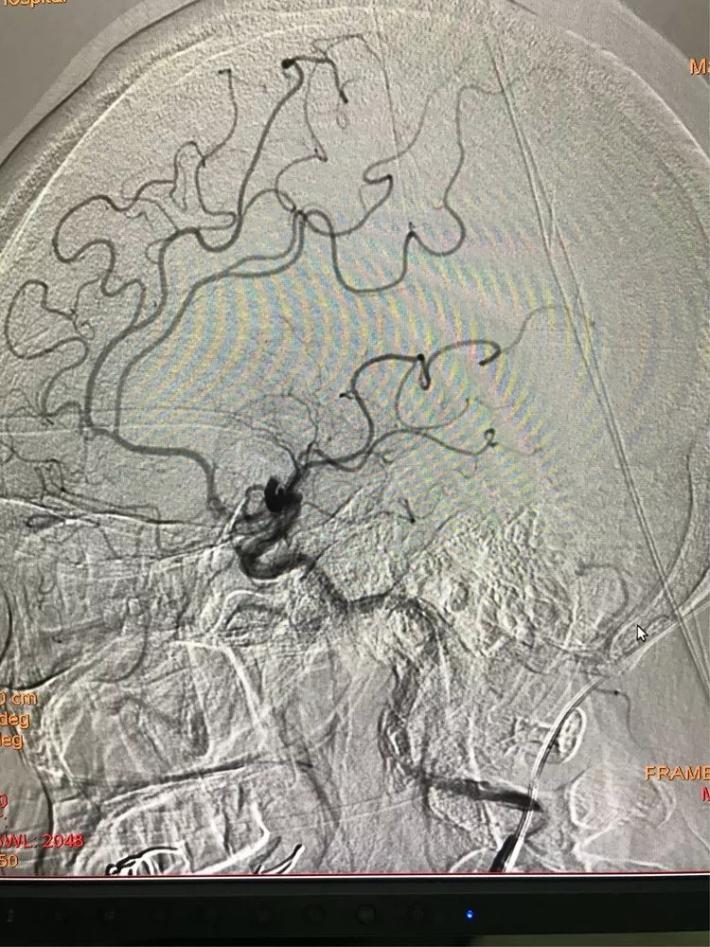

脑血管造影显示:右侧大脑中动脉闭塞。

手术步骤

微导管进入大脑中动脉远端真腔。

置入支架,见大脑中动脉有血流。

取出支架,血管未开通。

再次上微导管。

微导管进入大脑中动脉远端真腔。

第二次置入支架取栓。

血管仍未开通。

第三次上微导管。

再次置入支架取栓。

见血管再通。

支架和取出来的血栓。